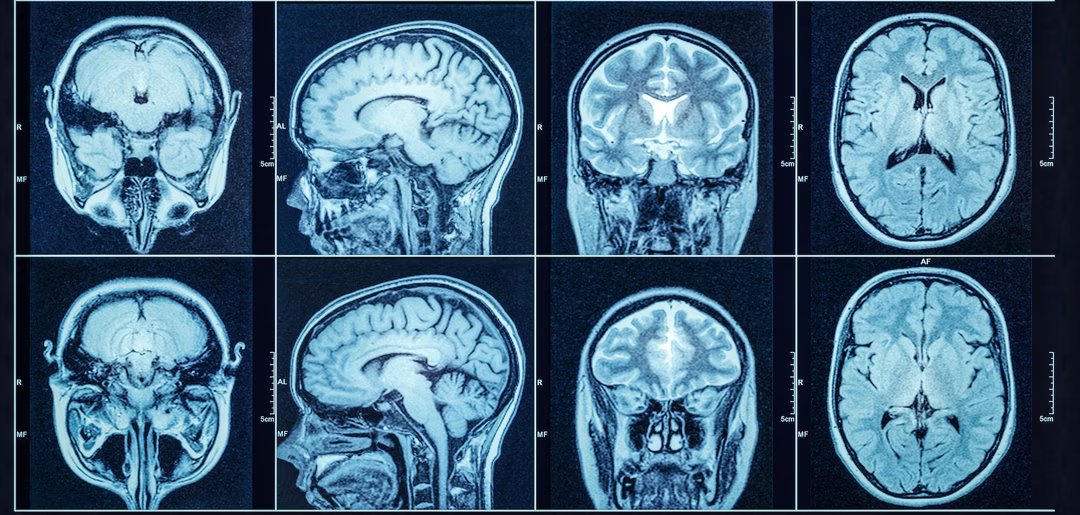

As ressonâncias magnéticas cerebrais estão cheias de informações, mas muitas delas permanecem inutilizáveis hoje. A causa: dados difíceis de interpretar, incompletos ou muito complexos para as ferramentas atuais. Um estudo publicado em Neurociência da Natureza apresenta uma solução inesperada, que poderá redefinir o papel da IA na medicina.

CérebroIAC apresenta desempenho notável, desde imagens até os complexos desafios da genética tumoral. © Tryfonov, Adobe Stock